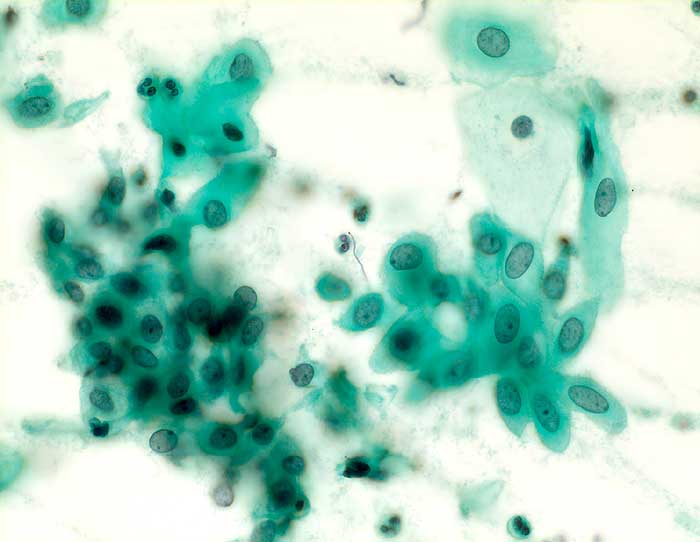

Nicht klassifizierbare Plattenepithelien (ASCUS)

Die Kategorie "atypical squamous cells of undetermined significance" der Bethesda Klassifikation umfasst entzündliche, reaktive und nicht klassifizierbare Plattenepithelveränderungen. Die Atypien übersteigen dabei das Mass gewöhnlicher reparativer Veränderungen. In den meisten Fällen sind reife Plattenepithelien betroffen. Nicht klassifizierbare Plattenepithelveränderungen können aber auch in metaplastischen oder atrophen Epithelien angetroffen werden. Die Diagnose ASCUS im atrophen Abstrich kann dann gestellt werden, wenn die Kerne mindestens zweimal so gross sind wie normal und eine deutliche Hyperchromasie zeigen, die Kernkontur bzw. Chromatinverteilung unregelmässig ist oder eine deutliche Pleomorphie in Form von Tadpole Zellen oder spindeligen Zellen vorhanden ist. In solchen Fällen kann nach einer kurzfristigen lokalen Östrogenbehandlung der Abstrich wiederholt werden. Gutartige atrophieassoziierte Veränderungen verschwinden unter Östrogentherapie. Signifikante präkanzeröse Läsionen persistieren hingegen und sind auf dem Hintergrund ausgereifter Zellen besser erkennbar.